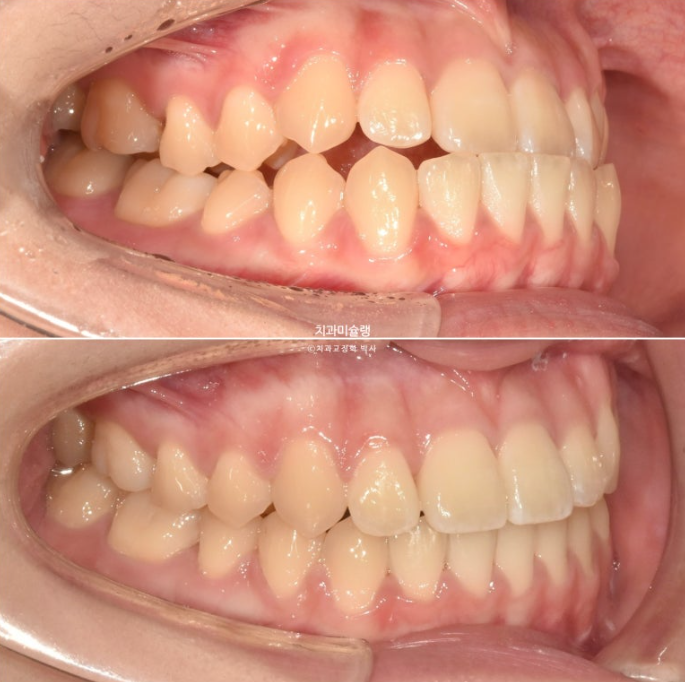

개방교합은 해소가 되었습니다.

23.09~25.07

교합은 1급 교합관계를 보입니다.

아랫니가 뒤로 들어가면서 앞니가 거꾸로 물리는 상태 즉 반대교합은 해소되었습니다.